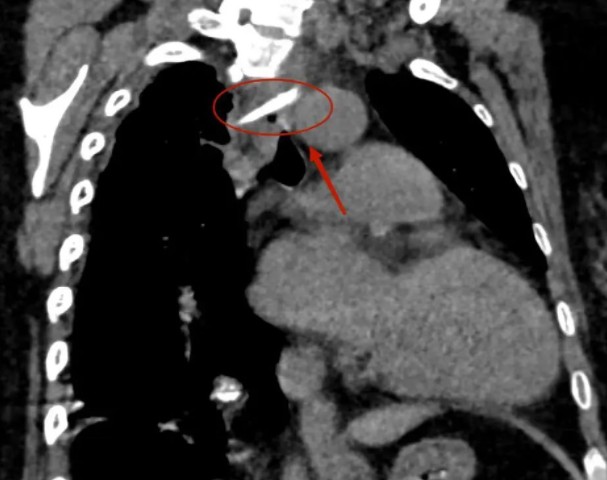

影像学上,

骨片异物两端紧贴主动脉和奇静脉。

当天行政值班的医务处副处长李磊得知情况,立即联系医疗总值班、影像科主任曹伟前来会诊。梭形长条骨片,边缘锋利,一端紧贴主动脉弓,一端顶着奇静脉,靠近奇静脉端的肺表面已经有些渗出,曹伟心里一沉。作为临床治疗的“眼睛”,影像诊断常被称为临床手术的“路标”,为了给临床提供更准确、直观的数据,曹伟对图像进行三维重建,将骨片的体积、长度、角度及骨片与周围组织的空间关系重新构建,这也为下一步治疗方案提供了依据。经过会诊后达成初步意见,患者收入心胸外科,在完善开胸手术准备的保驾下全麻内镜取异物。